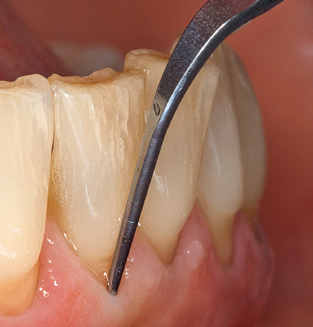

Following machine cleaning of the tooth and implant surfaces, the surfaces of the natural teeth are cleaned manually using standard hand instruments. When performing manual cleaning, particular attention must be given to maintaining the correct angle of application, appropriate sharpness, good support and working with the curette from apical to coronal. Either titanium or carbon curettes should be used for post-cleaning of the implant structures (Fig. 8). In addition to the use of ultrasonic devices, power jet devices can also be used in conservative dentistry. However, it must be taken into consideration that these procedures are not suitable for removing hard deposits and thus they cannot replace the use of hand instruments and ultrasonic instruments completely. In all cases, cleaning is followed by mechanical polishing of the accessible tooth and implant surfaces with polishing cups and polishing compounds (Fig. 9).

Fig. 4: Flexible probes with millimetre markings are recommended for the probing of dental implants (e.g. Colorvue Kit PCV11KIT6, Hu­Friedy). – Fig. 5a and b: A straight working tip (1P, W&H Dentalwerk Bürmoos GmbH) is a suitable instrument for use on all natural teeth. – Fig. 6: Curved working tips (3Pr/3Pl, W&H Dentalwerk Bürmoos GmbH) lend themselves to the processing of difficult-to-reach areas of the tooth and root surfaces (e.g. furcations). – Fig. 7: The tapered, hexagonal implant cleaning tip (1I, W&H Dentalwerk Bürmoos GmbH) permits atraumatic and efficient cleaning of the crown and abutment surfaces. – Fig. 8: Titanium and carbon curettes are suitable instruments for the manual cleaning of the implant surfaces.

An array of special carbon, titanium and plastic curettes and scalers are available for the mechanical cleaning of implant surfaces by hand.(13-15) Overall, the efficacy of the biofilm removal with the available hand instruments is predominantly assessed as ineffective.(11) Whilst plastic curettes in particular have only a minimal detrimental effect on the implant surface and afford patients a high degree of comfort, their poor efficiency with regard to biofilm removal and their incapacity to remove calculus and subgingival concretions contraindicate their use.(16,17) Today, the use of carbon and titanium curettes is viewed as being more efficient, with the result that, if at all, these can be recommended for use as hand instruments.(11)